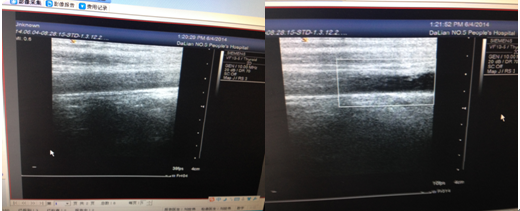

既往由于彩超的噪音干扰,血管管腔内极易出现透声差,甚至假阳性,我院西门子Antares彩超具有血管增强技术,又称数字减影技术(VET技术),启用VET技术后,可清晰显示患者颈动脉血管腔及管壁结构,尤其对早期血管内中膜IMT轻度增厚患者,能精确测量IMT;对已有斑块形成者,可清晰显示斑块表面特征及内部回声结构。

VET的原理是利用二维和彩色多普勒能量图的信息进行超声血管数字减影,从而更清晰地显示血管壁的细微结构。它提高了超声显像技术在血管疾病方面的诊断能力,拓展了超声显像技术在血管疾病方面的应用范围.

大量研究显示,低回声的软斑块含丰富的脂质,少量纤维组织及钙盐沉积,稳定性差,易发生斑块表面纤维帽破裂、斑块内出血。VET能准确反映颈动脉IMT的变化及颈动脉斑块是否形成。对无症状患者,一旦发现颈动脉内中膜增厚,可及早提示临床做出预防和治疗;对已经形成颈动脉斑块者,可利用VET技术定期复查评价临床

治疗效果,为临床预防脑梗塞提供客观依据。